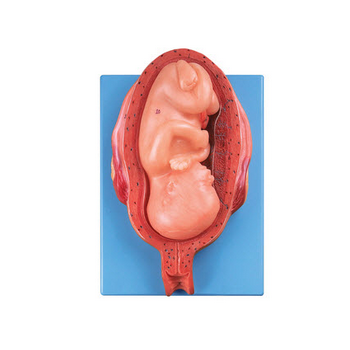

GD/A42006骨盆含妊娠九個月胎兒模型產品介紹:1、該模型由骨盆子宮和妊娠九個月胎兒兩個部件組成,并顯示子宮、陰道、膀胱、直腸和胎兒、羊膜、胎盤、臍帶等結構,共有38個部位指示標志。2、尺寸:自然...